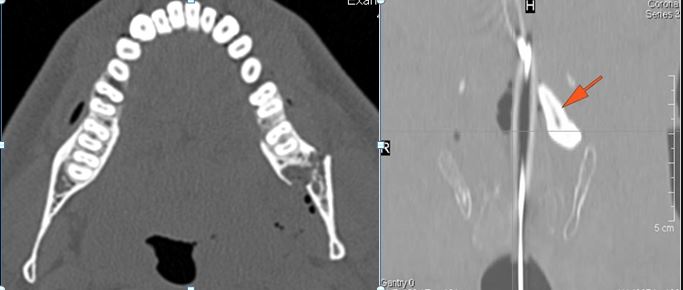

There is bony injury or displacement of the body, angle, ramus, parasymphyseal region, alveolar ridge, and condylar and coronoid process of the mandible. [In case of fracture, describe complexity and displacement].

There is bony injury or displacement of the external auditory canal and/or other evidence of temporal bone injury.